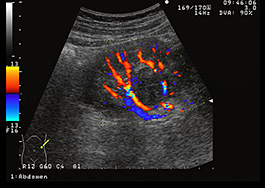

イメージング

画像検査は、腎細胞癌の診断と病期分類に役立ちます。

• MRIおよびCT スキャンは、腫瘍の位置とサイズを示すことができます。